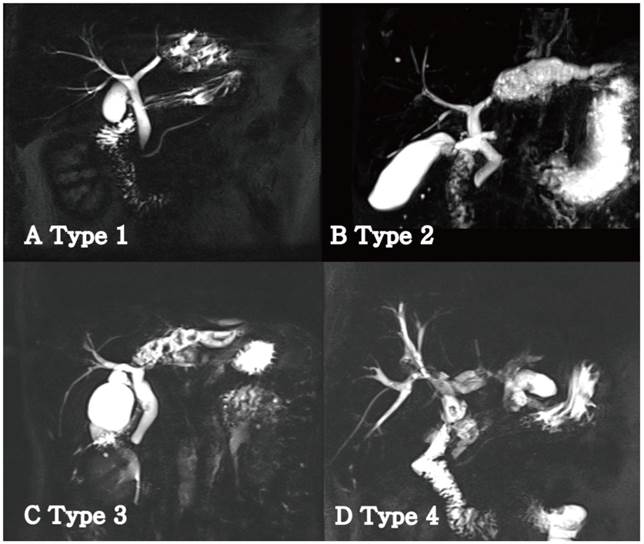

The disease classification and operative strategy was based on the extent of atrophy of the left lobe and position of the left biliary strictures. The atrophic changes were classified as follows: unclear atrophy on CT, mild atrophy with only one segment among segments II to IV or overall mild atrophy, moderate atrophy with more than 50% atrophy in the left lobe, and severe atrophy with almost no normal hepatic parenchyma. Left biliary strictures were classified into the following four types to provide a more accurate description (Fig. 1) [4]: type 1, strictures were located distally rather than in the bifurcation of B4 and B2+3 with noted dilatation of only B2+3 in most cases; type 2, strictures were located in the bifurcation of B4 and B2+3 or in the proximal bifurcation of B4 and B2+3 with dilatation of the entire left intrahepatic bile ducts (in these cases, severe atrophy of the left hepatic parenchyma and relative hypertrophy of the caudate lobe were commonly observed); type 3, the presence of strictures or stones in the bile ducts of the caudate lobe; and type 4, the presence of strictures in both hepatic lobes.

Classification of the left hepatic strictures in patients with left-sided hepatolithiasis. (A) Type 1: Stricture was confined to one segment. B2+3 was usually involved. (B) Type 2: Stricture was located near the confluence of B4. B4 and B2+3 were concurrently dilated. (C) Type 3: Stricture was extended to the caudate duct portion. Concomitant resection of the caudate lobe was usually performed in the biliary stricture of this type. (D) Type 4: Multiple stones and strictures existed in the right and left lobes.